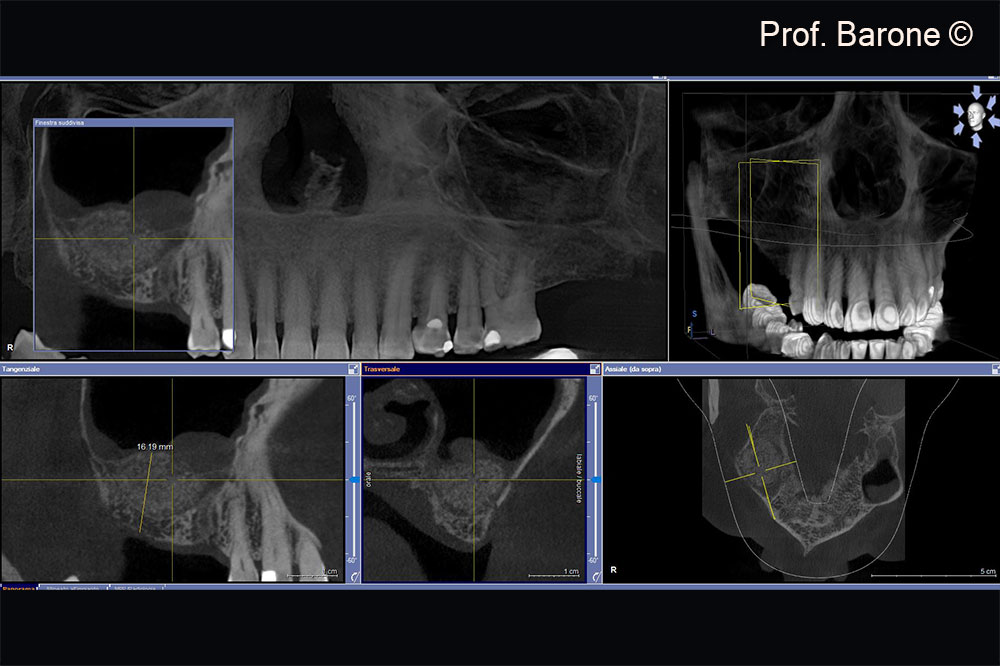

Residual ridge height doesn’t allow implant placement

Residual ridge height doesn’t allow implant placement, sinus membrane hypertrophy